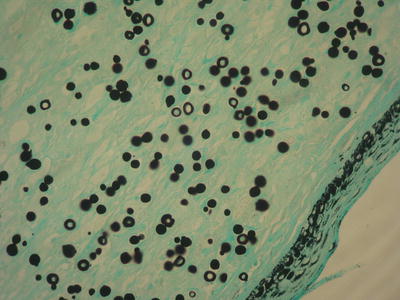

Diagnosis is made by direct microscopic examination. A pathological examination will show the presence of lymphocytic infiltrate and round fungal structures with birefringent walls, isolated or grouped in the form of chains (Figs. 4.21 and 4.22) . To date, no one can grow the Lacazia loboi fungus in culture medium. There is an antigenic resemblance between the fungi Lacazia loboi and Paracoccidioides braziliensis .

Fig. 4.21

Jorge Lobo’s disease: skin biopsy, hematoxylin–eosin staining

Fig. 4.22

Jorge Lobo’s disease: skin biopsy, silver-methenamine staining